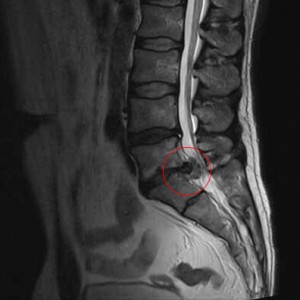

Résorption spontanée de l’hernie discale lombaire : Une étude scientifique d’importance !

Résorption spontanée de l’hernie discale lombaire : Une étude scientifique d’importance ! Une étude scientifique d’intérêt « Incidence of Spontaneous Resorption of Lumbar Disc Herniation: A Meta-Analysis » (1) vient d’être publiée sur l’incidence des résorptions non chirurgicales des hernies discales lombaires. Elle fait actuellement beaucoup de bruit dans le domaine médical. Il s’agit d’une revue systématique de la littérature […]